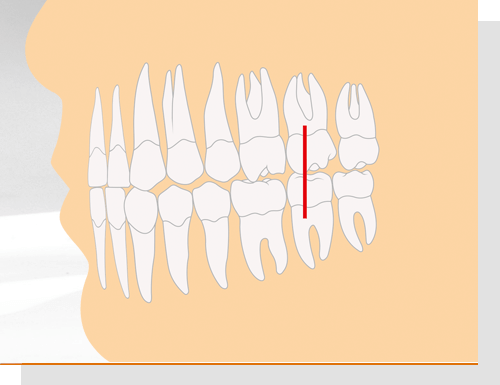

Angle-Klasse II

Die Angle-Klasse II beschreibt einen Überbiss. Der vordere Höcker des ersten großen Backenzahns im Oberkiefer beißt dabei vor den ersten großen Backenzahn im Unterkiefer. Man spricht daher auch vom Distal-Biss, also einem Zusammenbiss, der zu weit in Richtung des Endes der Zahnreihe verschoben ist. Je nach Stellung der Schneidezähne unterscheidet man zwischen Angle-Klasse II/1 und Angle-Klasse II/2: